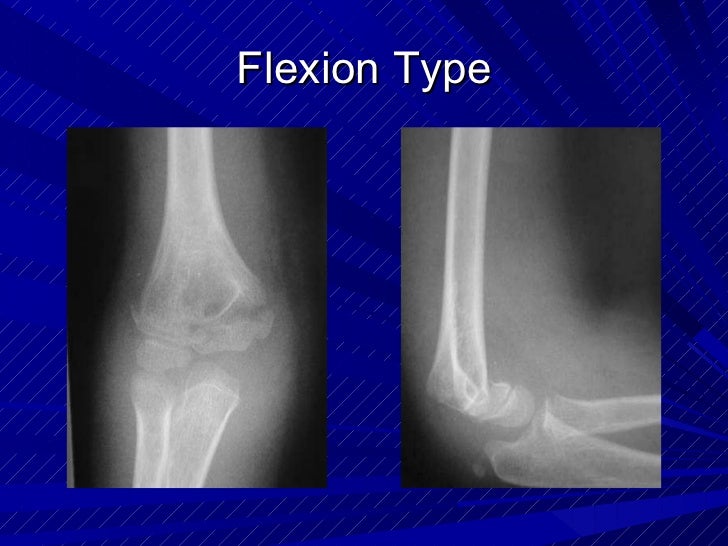

Cureus Surgical Management of Flexion Type Supracondylar Humeral Extension Type Supracondylar Fracture Orthobullets Find out the indications, techniques and complications. The gartland classification of supracondylar fractures of the humerus is based on the degree and direction of displacement, and the presence of intact cortex. Learn about the anatomy, classification, diagnosis and treatment of distal humerus fractures, including supracondylar fractures. There are two types of supracondylar fractures: Learn about the epidemiology, imaging, and treatment. Extension Type Supracondylar Fracture Orthobullets.

Supracondylar fractures in_children Extension Type Supracondylar Fracture Orthobullets Learn about the epidemiology, imaging, and treatment of supracondylar fractures in children, a common elbow injury from a fall. Generalized swelling about the elbow could be present;. The gartland classification of supracondylar fractures of the humerus is based on the degree and direction of displacement, and the presence of intact cortex. There are two types of supracondylar fractures: Find out. Extension Type Supracondylar Fracture Orthobullets.